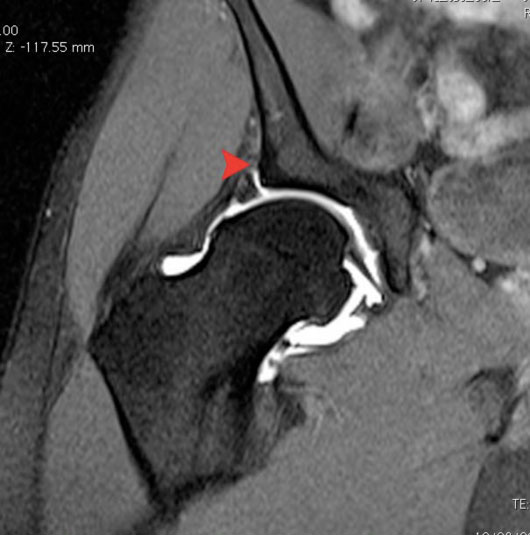

Although X rays can suggest the diagnosis of labral tears by identification of the causative condition, an MR arthrogram is the diagnostic examination of choice. Although labral detachments are frequently not picked up with this technique when combined with an intraarticular injection of a local anesthetic, the hip can be identified as the source of pain.

(MRI arthrogram of the hip demonstrating a labral tear. The red arrow demonstrates where the labrum is torn away from the acetabulum)